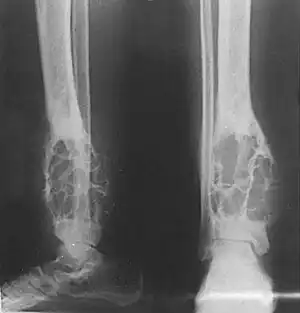

| X-ray (side and front views) showing an adamantinoma in the large bone of lower leg, near the ankle. | |

X-rays of the affected area show a well defined tumor in bone, with multiple lobules giving a "soap bubble" appearance.[2] MRI can provide a more useful guide to its severity.[2]

X-rays of the affected area show a well defined tumor at the edge of the bone, with multiple lobules giving a "soap bubble" appearance.[2] MRI can provide a more useful guide to its severity.[2]